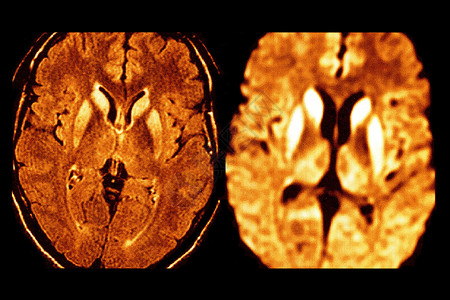

低血糖的 mri 表现,左图 t2 加权像示尾状核头,豆状核及皮层高泻排

cjd 典型 mri 表现:t2 加权像和 dwi 提示双侧尾状核,壳核,丘脑内侧